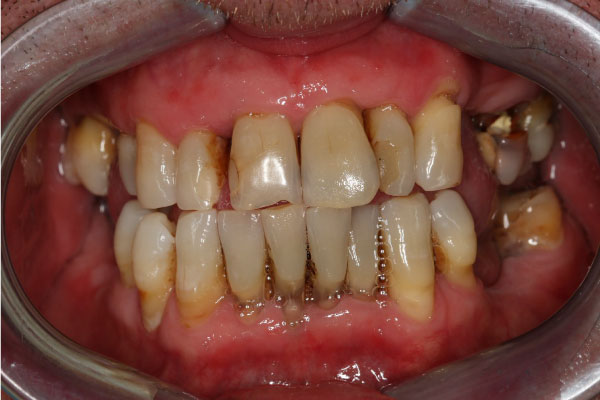

Имплантация зубов: фото "До" и "После"

Фото ДО

Фото ПОСЛЕ

Наведите для просмотра

All-on-4